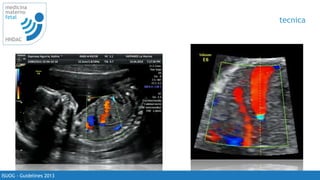

tecnica

• corte axial: talamos y base dek esfenoides

• visualizar el vaso y tomar la muestra lo mas

cercano a la carótida interna

• tomar 3 - 10 ondas

• lograr lo posible un angulo cercano a 0